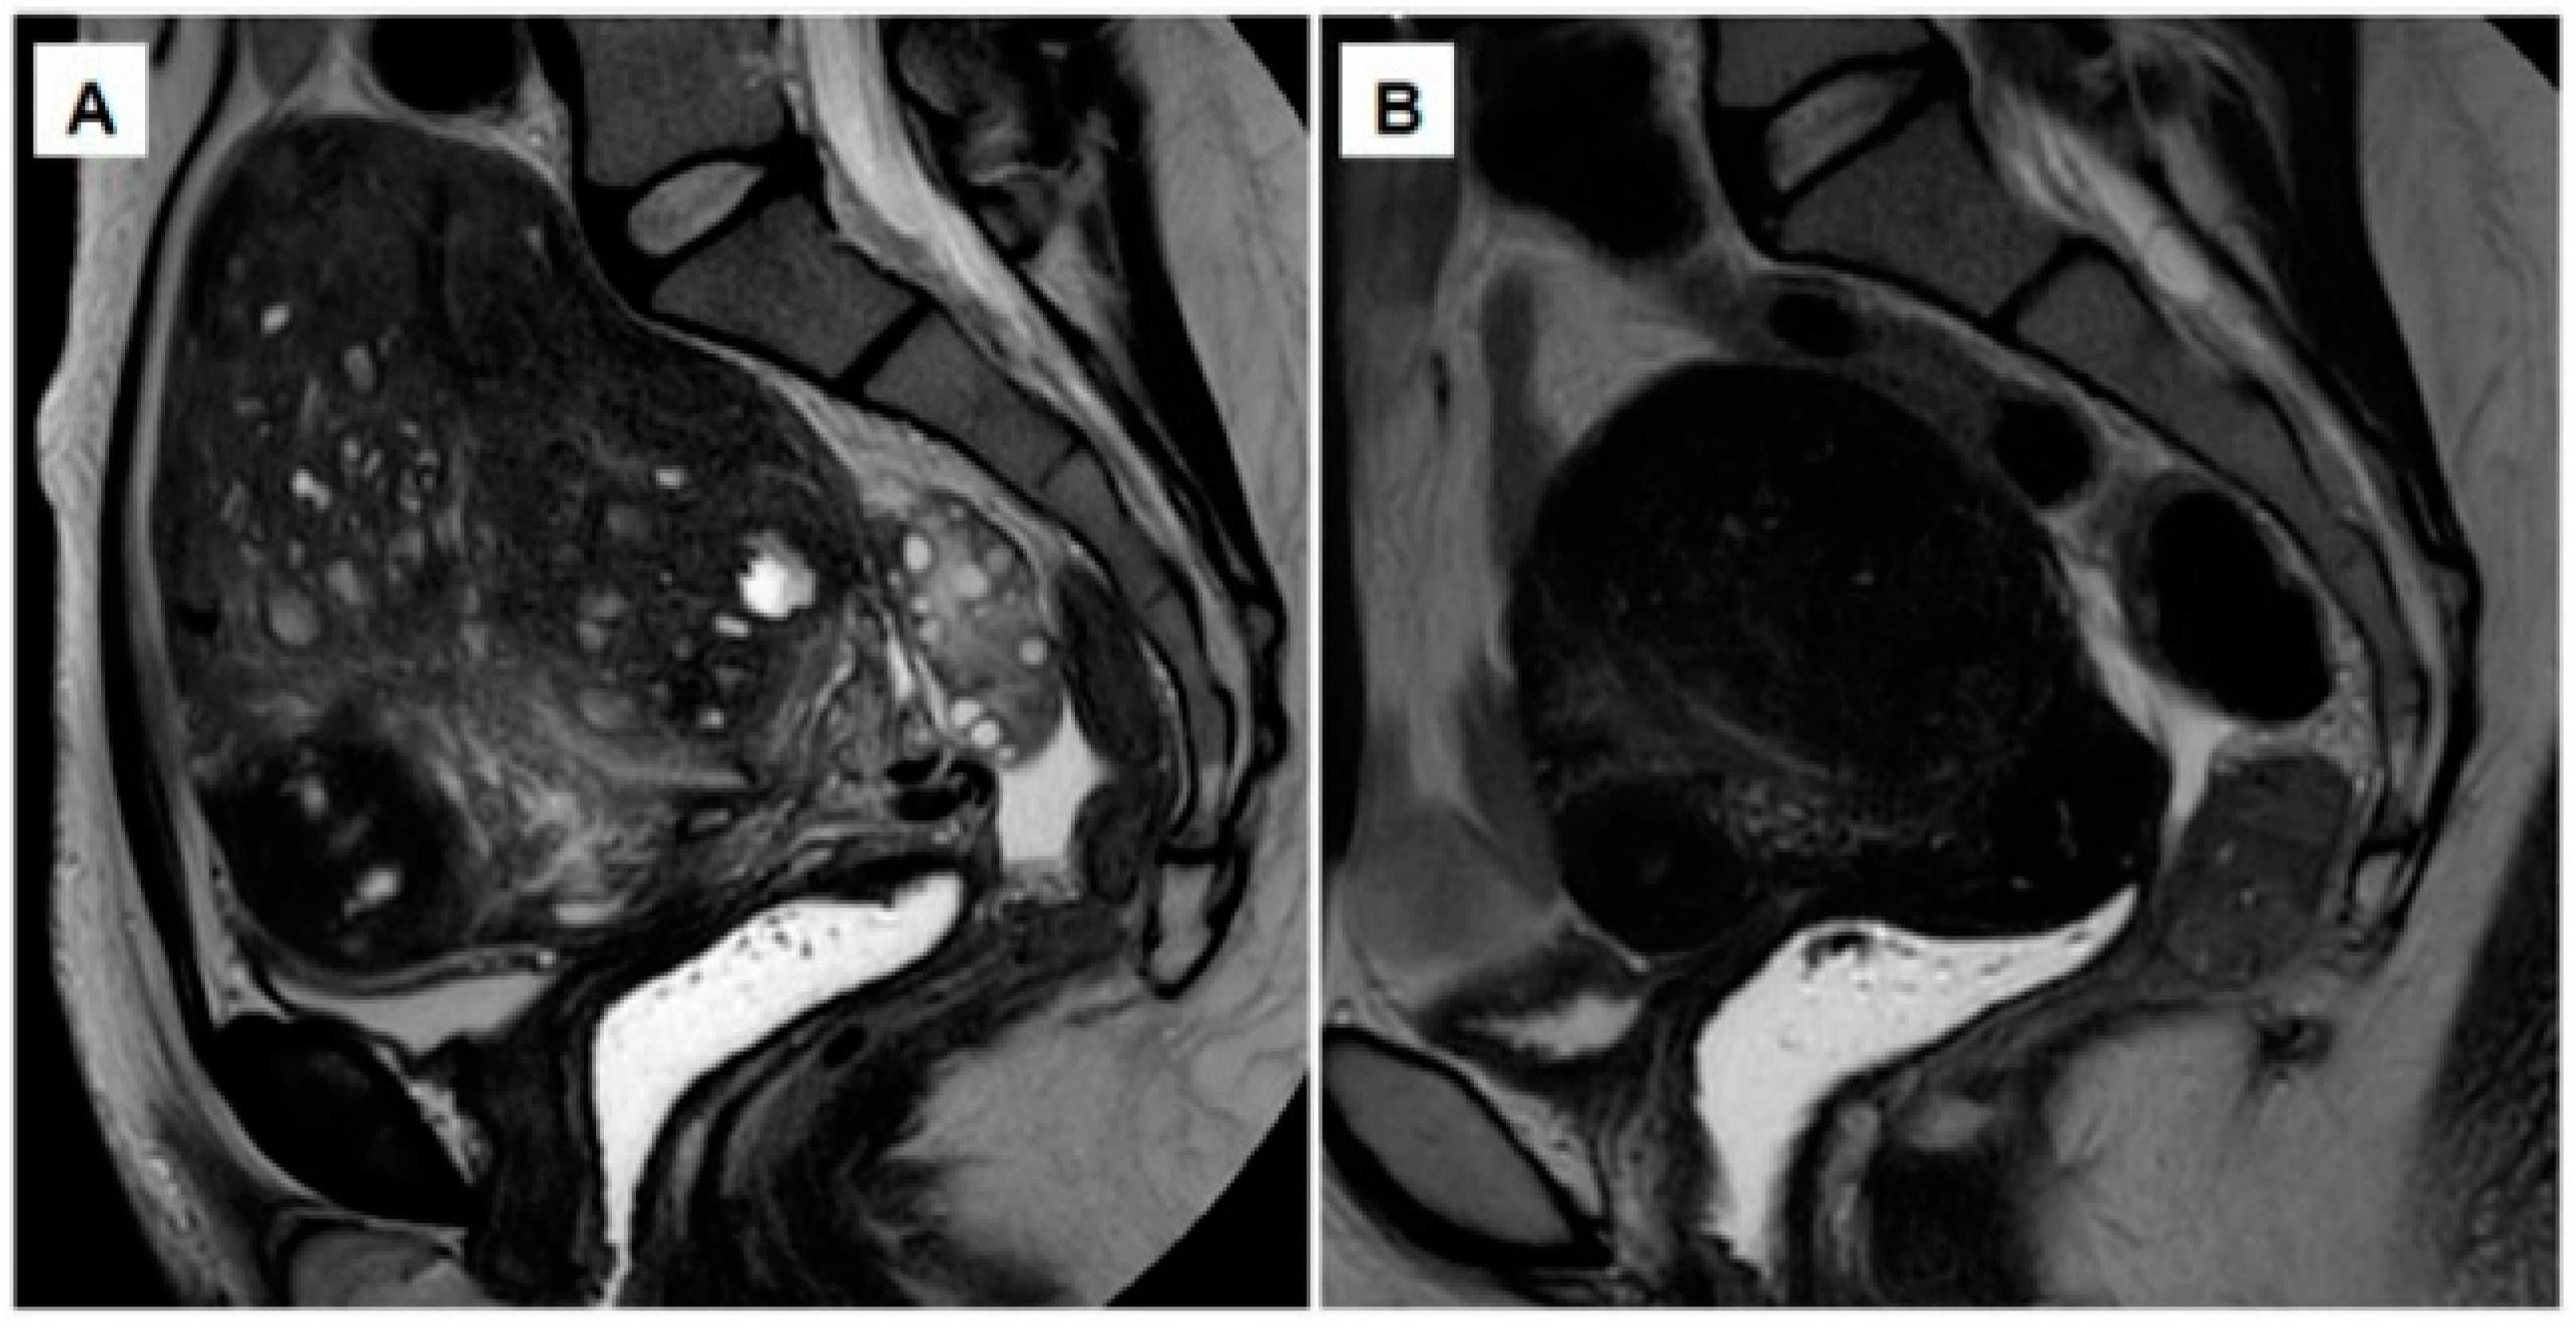

- Donnez, O.; Donnez, J. Gonadotropin-releasing hormone antagonist (linzagolix): A new therapy for uterine adenomyosis. Fertil. Steril. 2020, 114, 640–645. [Google Scholar] [CrossRef]

- Donnez, J.; Donnez, O.; Brethous, M.; Bestel, E.; Garner, E.; Charpentier, S.; Humberstone, A.; Loumaye, E. Treatment of symptomatic uterine adenomyosis with linzagolix, an oral gonadotropin-releasing hormone receptor antagonist: A pilot study. Reprod. Biomed. Online 2021. [Google Scholar] [CrossRef]